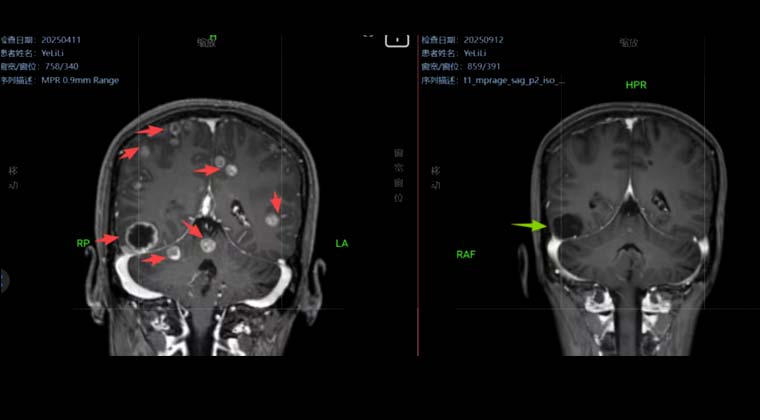

Пациентка, 38 лет

Комплексное лечение рака прямой кишки на протяжении почти 3 лет, головные боли в течение более 1 месяца.

Диагноз: Множественные метастазы в головной мозг при раке прямой кишки (стадия IVB, HER-2-положительный). Ранее проведённая химиотерапия и таргетная терапия оказались неэффективными, выявлены множественные внутримозговые метастатические очаги.

В апреле 2025 года в нашей клинике выполнена SBRT (стереотаксическая радиохирургия HyperArc) по поводу очагов в головном мозге, 40 Гр / 10 фракций.

Через 5 месяцев после лечения контрольное МРТ головного мозга показало практически полное исчезновение опухолевых очагов (G-PR). Качество жизни пациентки хорошее.

Изображение слева: до лечения

Изображение справа: после лечения